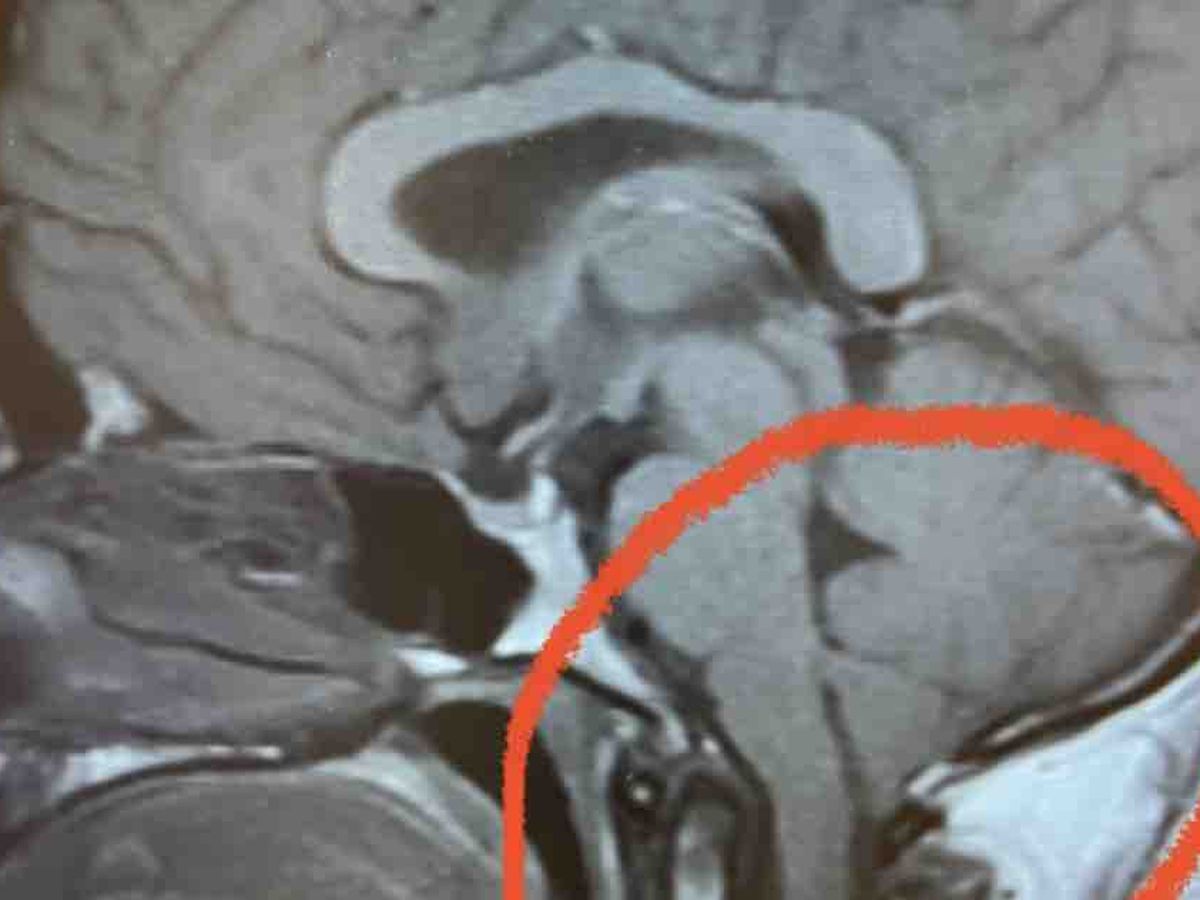

I am fundraising for unplanned medical expenses that I now have on the horizon. In the beginning of November, I was having intensifying episodes of headaches, dizziness, nausea, and high pressure “brain squeezes” which prompted me to contact my GP. After a whole line of investigative work, including multiple MRIs and tests, I was diagnosed with Chiari malformation type 1. This means that the back lower part of my brain known as the cerebellum is slightly going down in to my spine. This is causing crowding at the base of my skull which creates the unbearable pressure and relating symptoms.

My neurosurgeon mentioned that a pressure release surgery would help with symptoms. This will allow more space for my cerebellum to be. So, on January 11 I will be having a craniotomy and laminectomy.